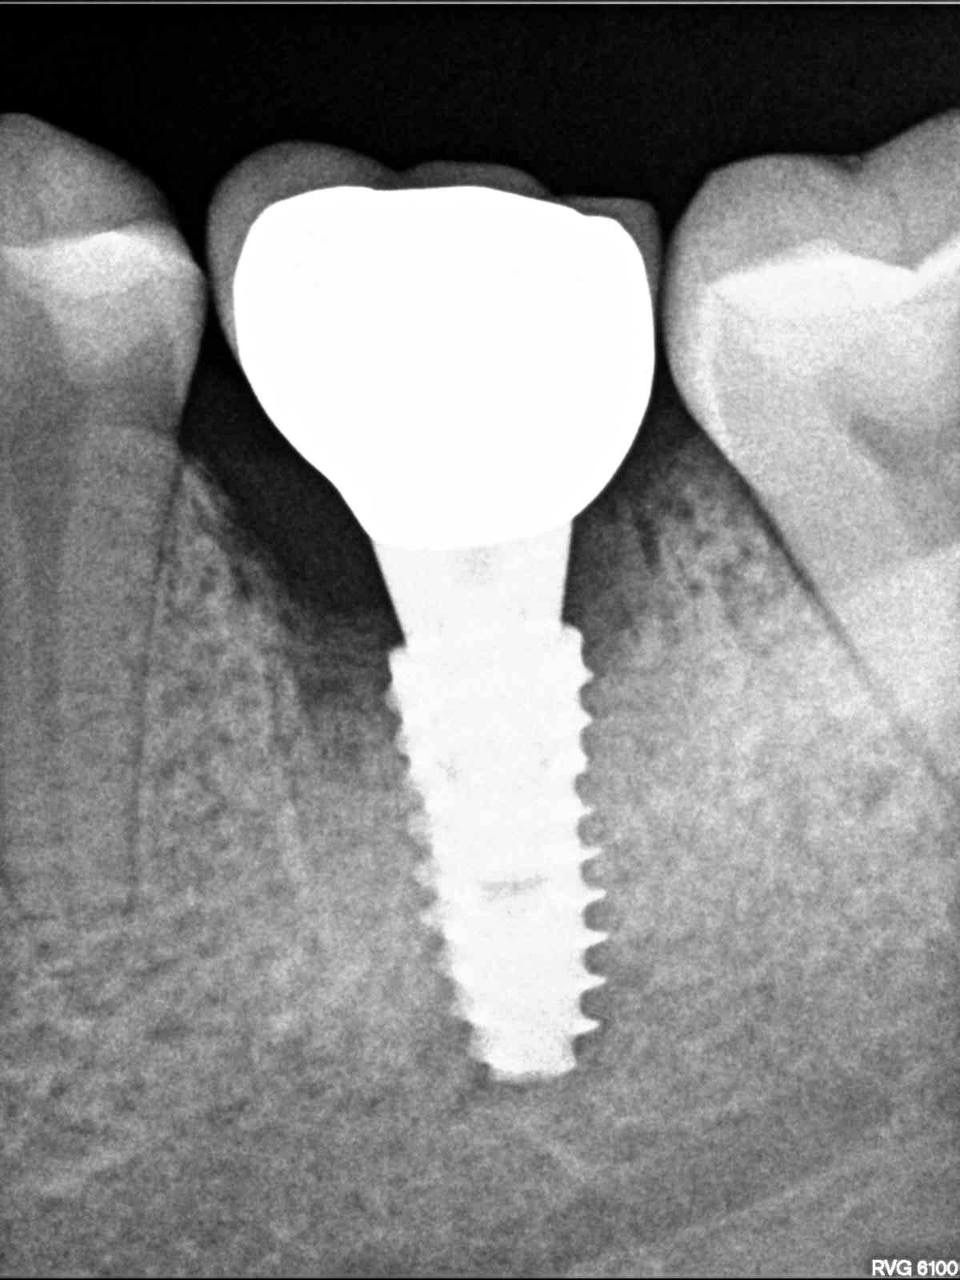

Одномоментная имплантация — Исламов Л.А.(10.11.2025)

Одномоментная имплантация системой Osstem(Ю. Корея), подшит трансплантат с бугра(для увеличения объема мягких тканей), установлен формирователь десны. Через 3 месяца установлена коронка из диоксида циркония на винтовой фиксации